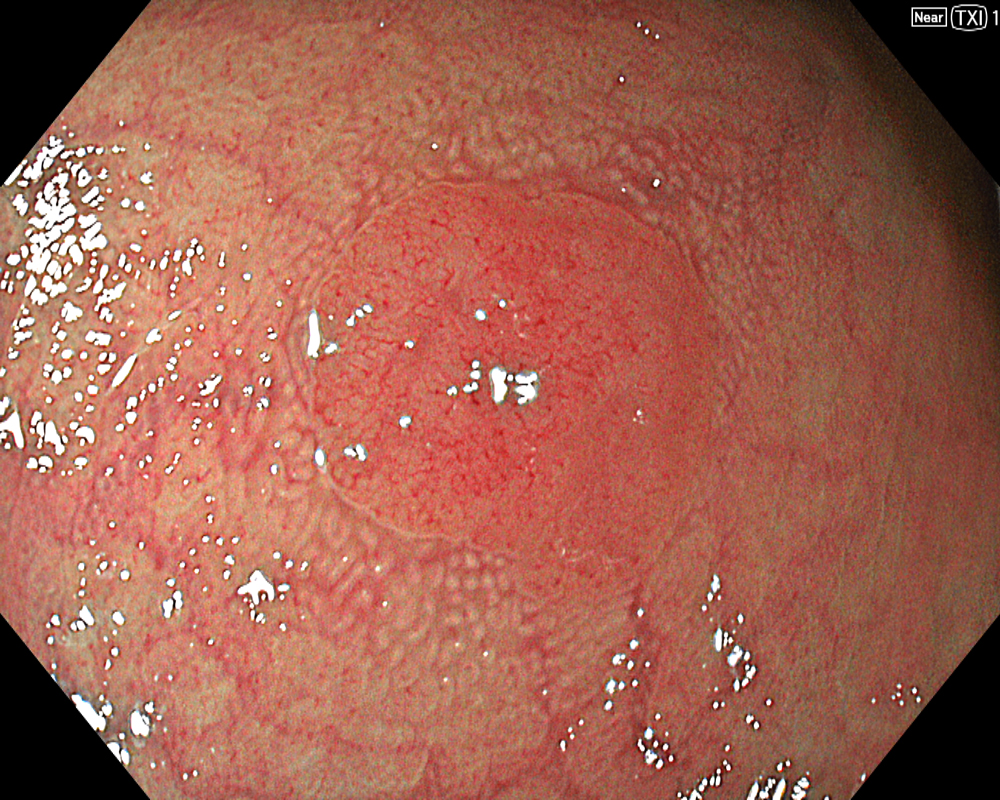

Figure 3: NBI image in near-focus mode under water immersion. Water immersion eliminates halation and provides clear images, while also enhancing magnification for more detailed observation.

In addition to eliminating halation, underwater observation has a magnification effect. When combined with the Near focus mode, it allows for even clearer magnified images. For determining the indication for CSP, the JNET (Japan NBI Expert Team) classification is used, which evaluates the surface Vessel pattern and Surface pattern using NBI + Near focus magnified observation. If the lesion is classified as Type 2A (characterized by a regular caliber and regular distribution (meshed/spiral pattern) in the Vessel pattern, and a regular pattern (tubular/branched/papillary) in the Surface pattern), it is highly likely to be a lowgrade intramucosal neoplasia, and CSP can be indicated if the size is less than 10 mm. If the lesion is classified as Type 2B (characterized by variable caliber and irregular distribution in the Vessel pattern, and an irregular or obscure pattern in the Surface pattern), there is a higher possibility of high-grade intramucosal neoplasia or deeper invasion. Indiscriminately performing CSP based solely on small size should be avoided in these cases.